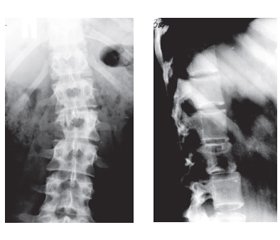

Найбільш актуальними питаннями хірургічного лікування пухлин залишаються онкологічний радикалізм (обсяг оперативного лікування) й тактика відновлення опорної функції хребта. Мета роботи: проаналізувати результати хірургічного лікування пацієнтів із первинними пухлинами грудного й поперекового відділів хребта за відповідними оціночними шкалами. Матеріали та методи. Під клінічним спостереженням були 43 пацієнти з доброякісними і злоякісними первинними пухлинами й пухлиноподібними ураженнями хребта, які знаходилися на лікуванні у відділенні вертербрології Інституту патології хребта і суглобів ім. проф М.І. Ситенка НАМН України. Локалізація уражень була такою: шийний відділ хребта — 5 пацієнтів, грудний — 17, поперековий — 19, крижі — 2. Серед хворих були 22 жінки й 21 чоловік, вік пацієнтів — 18–72 роки. За патоморфологічною класифікацією первинних пухлин і пухлиноподібних уражень ВООЗ пацієнтів розподілили так: доброякісні пухлини — 26 осіб, злоякісні — 17. Результати хірургічного лікування первинних пухлин хребта аналізували з використанням шкал ASIA, SINS, Bilsky, також ураховувалася локалізація пухлин у різних сегментах хребтового стовпа. Результати. Оцінку результатів хірургічного лікування пухлин хребта ми проводили за такими показниками: радикальне хірургічне втручання, наявність ускладнень, динаміка неврологічних та ортопедичних порушень, наявність рецидивів пухлини й тривалість життя пацієнтів. Радикальне видалення пухлини в межах здорових тканин було досягнуте в 17 з 19 пацієнтів, у яких були показання до застосування цього методу хірургічного лікування. У 24 пацієнтів провели оперативне лікування у вигляді декомпресії хребетного каналу й часткову резекцію пухлини для відновлення опорної функції хребта. У 2 випадках досягти абластичності не вдалося. Висновки. За показниками шкал ASIA, SINS, Birsky установлено, що оперативне втручання при первинних пухлинах хребта є виправданим, дозволяє запобігти неврологічним ускладненням, істотно зменшує наявні неврологічні розлади, а також продовжує життя пацієнтів. Вибір обсягу хірургічного втручання, направленого на відновлення опорної функції хребта, за цими шкалами не показаний. Лікування первинних пухлин хребта повинно включати як радикальне видалення атипових тканин у межах здорових, так і паліативне лікування за показаннями. Важливе відновлення опорної функції хребта в зоні його пошкоджених сегментів.

Наиболее актуальными вопросами хирургического лечения опухолей остаются онкологический радикализм (объем оперативного лечения) и тактика восстановления опорной функции позвоночника. Цель работы: проанализировать результаты хирургического лечения пациентов с первичными опухолями грудного и поясничного отделов позвоночника с использованием соответствующих оценочных шкал. Материалы и методы. Под клиническим наблюдением были 43 пациента с доброкачественными и злокачественными первичными опухолями и опухолеподобными поражениями позвоночника, которые проходили лечение в отделении вертебрологии Института патологии позвоночника и суставов им. проф. М.И. Ситенко НАМН Украины. Локализация поражений была такой: шейный отдел позвоночника — 5 пациентов, грудной — 17, поясничный — 19, крестец — 2. Среди больных были 22 женщины и 21 мужчина, возраст пациентов — 18–72 года. В соответствии с патоморфологической классификацией первичных опухолей и опухолеподобных поражений ВОЗ пациенты распределились следующим образом: доброкачественные опухоли — 26 пациентов, злокачественные — 17. Результаты хирургического лечения первичных опухолей позвоночника проанализированы с использованием шкал ASIA, SINS, Bilsky, также учитывалась локализация опухолей в различных сегментах позвоночного столба. Результаты. Результаты хирургического лечения опухолей позвоночника мы оценивали по следующим показателям: радикальное хирургическое вмешательство, наличие осложнений, динамика неврологических и ортопедических нарушений, наличие рецидивов опухоли и продолжительность жизни пациентов. Радикальное удаление опухоли в пределах здоровых тканей было достигнуто у 17 из 19 пациентов, у которых были показания для использования данного метода хирургического лечения. У 24 пациентов провели оперативное лечение в виде декомпрессии позвоночного канала и частичную резекцию опухоли для восстановления опорной функции позвоночника. В 2 случаях достичь абластичности не удалось. Выводы. На основании данных шкал ASIA, SINS, Birsky установлено, что оперативное вмешательство при первичных опухолях позвоночника является оправданным, позволяет предотвратить неврологические осложнения, существенно уменьшить существующие неврологические расстройства, а также продлить жизнь пациентов. Выбор объема хирургического вмешательства, направленного на восстановление опорной функции позвоночника, по данным этих шкал не показан. Хирургическое лечение первичных опухолей позвоночника должно включать как радикальное удаление атипичных тканей в рамках здоровых, так и паллиативное лечение по показаниям. Важно восстановление опорной функции позвоночника в зоне поврежденных сегментов позвоночника.

Oncological radicalism (the scope of surgical treatment) and restoration of the supporting function of the spine remain the most pressing issues of surgical treatment for tumors. Purpose of the work: to analyze the outcomes of surgical treatment of patients with primary tumors of the thoracic and lumbar spine based on the appropriate rating scales. Materials and methods. Forty-three patients, 22 women and 21 men aged 18 to 72 years, with benign and malignant primary tumors and tumor-like lesions of the spine were examined; they were treated at the Department of vertebrology of the Sytenko Institute of Spine and Joint Pathology of the National Academy of Medical Sciences of Ukraine. Localization of the lesions was as follows: cervical spine — 5 patients, thoracic — 17, lumbar — 19, sacrum — 2. According to the pathomorphological classification of primary tumors and tumor-like lesions of the World Health Organization, the patients were divided into those with benign (n = 26) and malignant (n = 17) tumors. The results of surgical treatment for primary spinal tumors were analyzed using the American Spinal Injury Association (ASIA) scale, Spinal Instability Neoplastic Score (SINS), Bilsky scale; the localization of tumors in different segments of the spinal column was considered as well. Results and discussion. We evaluated the outcomes of surgical treatment of spinal tumors for the following indications: radical surgery, the presence of complications, the dynamics of neurological and orthopedic disorders, the presence of tumor recurrence and the life expectancy of patients. Radical tumor resection within healthy tissues was performed in 17 of 19 patients, who had indications for the use of this method. Twenty-four patients underwent surgical treatment in the form of decompression of the spinal canal and partial tumor resection to restore the supporting function of the spine. In 2 cases, ablasticity was not achieved. Conclusions. According to the ASIA, SINS, Birsky scales, it was found that surgical intervention in primary tumors of the spine is justified, it prevents neurological complications, significantly reduces existing neurological disorders, and prolongs the life of patients. The choice of the scope of surgical intervention aimed at restoration of the supporting function of the spine according to these scales is not shown. Treatment of primary tumors of the spine should include both radical removal of atypical tissues within the healthy tissues and palliative treatment if indicated. It is important to restore the supporting function of the spine in the area of its damaged segments.